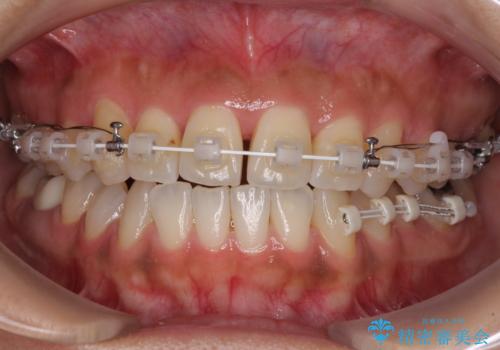

【モニター】幅の狭い上顎歯列 骨幅を拡大する矯正治療

上顎骨の横幅が狭く、歯列が混み合っていたため、急速拡大装置により側方拡大し、咬み合わせと歯列を改善することとしました。

骨格的な問題を解決したことで、下顎は部分矯正で対応することができました。